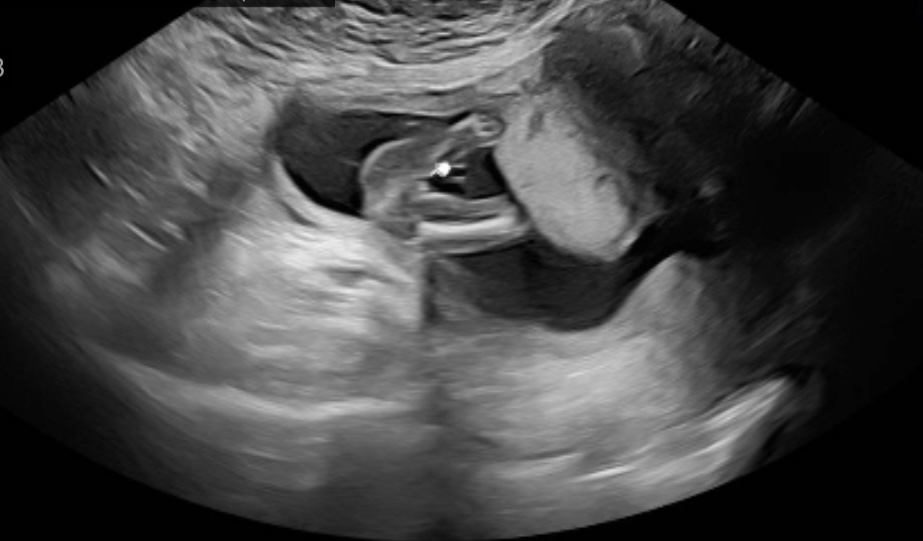

تحديد جنس الجنين الاسبوع ١٧

الصورة غير واضحة كثيرا ، عادة في تحديد الجنس احيانا يمكن تحديده من الاسبوع 14 حسب دقة الايكو ووضعية الجنين لكن جرت العادة ان يتم التحديد بعد 16 اسبوع حملي ومن خلال اكثر من مقطع وصورة يظهر فيها القضيب بالنسبة للذكر او الخطوط الثلاثة الموافقة للشفرين بالنسبة للانثى